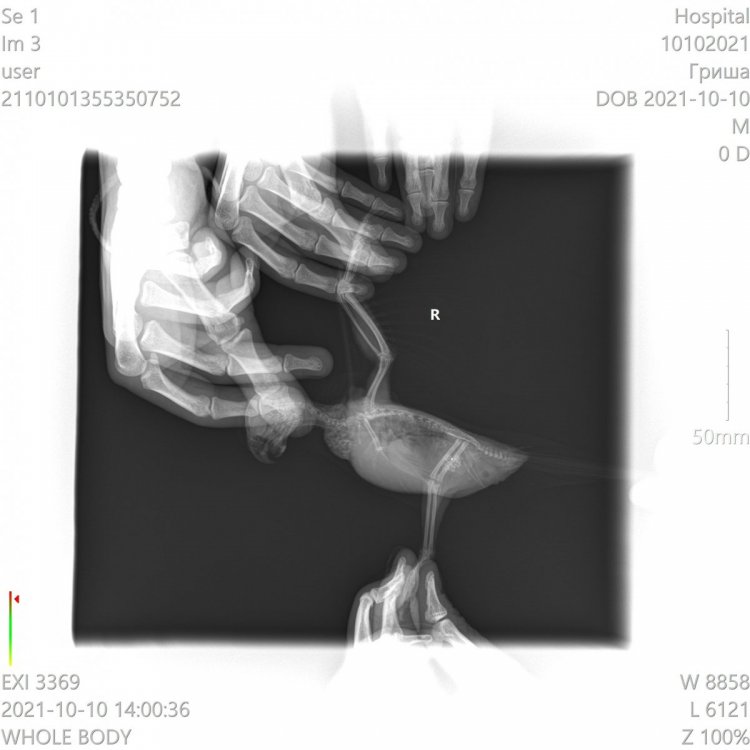

Возраст: 7 полных лет. Пол: женский. Порода: сизарь обыкновенный (Columba livia). Около 4-х месяцев назад голубка перестала нести яйца. Последние две пары снесенных яиц были значительно меньше обычных (не более 2 см.). Затем (в конце июля) появились странные выделения в помете (фото 1 и 2). Такие выделения начали выходить вместе с пометом примерно 1-2 раза в месяц. Когда у нее появляются эти странные выделения она ведет себя примерно так же, как во время кладки (хвост опущен, ищет место для кладки, разгребает, учащенно дышит). В остальное время голубка жизнерадостная и активная, ест и пьет хорошо, как обычно, летает, общается и т.д. Мы были у ветеринара, ей сделали рентген (фото 3 и 4). Доктор сказала, что у нее в брюшке эти сгустки - предположительно, остатки несформированного яйца. Эти сгустки могут накапливаться и давить на органы. Доктор предложила два способа решения: Инъекция (чего именно мы не знаем). При помощи этой инъекции, предположительно, голубка должна самостоятельно избавиться от этих сгустков, которые выйдут самостоятельно. Доктор сказала, что понаблюдает за ней в течение половины дня. Оперативное вмешательство. Если инъекция не подействует - доктор сказала что нужно будет делать операцию по очистке. Но при операции есть риск неудачного исхода. В общем от операции, над инъекцией думаем. Хотим собрать мнение еще нескольких специалистов, т.к. очень боимся возможного риска и не хотим сделать хуже. Пишу сюда, потому что хочу узнать мнения людей, встречавшихся с подобными ситуациями и так же мнения орнитологов и\или голубеводов, присутствующих на этом форуме. Заранее спасибо всем за ответ!- 3 ответа

Неразлучник перестал летать, когда посмотрела, обнаружила на внутренней стороне крыла шишечку, сделали рентген, фото прикладываю. Не летает, крыло отпустилось и дрожит, продолжается больше месяца, обратиться больше не к кому, у нас нет специалистов в городе. Помет у попугая не менялся, активность хорошая, кушает тоже хорошо -

г.Новодвинск. Специалистов нет. Проблема: плохо ходит, падает, не ест. Помет изменился. Предположение: застревания яйца Попугай корелла самка 6 лет. Клеточное содержание. Практически без выпуска из-за собаки,детей.Неслась практически ежегодно. Корм только РИО для средних попугаев, не ограничено. Съедала много.Пила воды много. Овощи, зелень, мин.подкормка,сепии и т.п. в рационе отсутствовали. На окне в клетке в комнате. Проблемы начались в начале недели, после того как снесла яйцо. Упала с жердочки, и практически перестала ходить. Обратились к девушке волонтеру по птицам. Единственному человеку который хоть как то попытался помочь и отправил сюда. Рекомендовано: Рентген(сделан), анализы( бак.посев,копрограмма) НЕ ДЕЛАЮТ в гор.вет.лаб. Обратиться к специалисту(поэтому тут). Улучшить условия кормления и содержания(делаем). Помогите спасти птицу,пожалуйста.Ошибки осознали..исправим,но очень нужна помощь. Назначено: вазелиновое масло 0,4мл в клоаку, 0,1мл в клюв 1 раз в сутки. . Водяная баня. Кормление насильно через шприц запаренной крупой с яблочным пюре детским. Глюконат кальция ампульный по 0,05мл 1 раз в сутки, клюв. Мильгамма 1/8 таблетки в клюв. Энтеросгель 0,1мл в разведении 1:1 с водой. Нужна помощь в лечении(